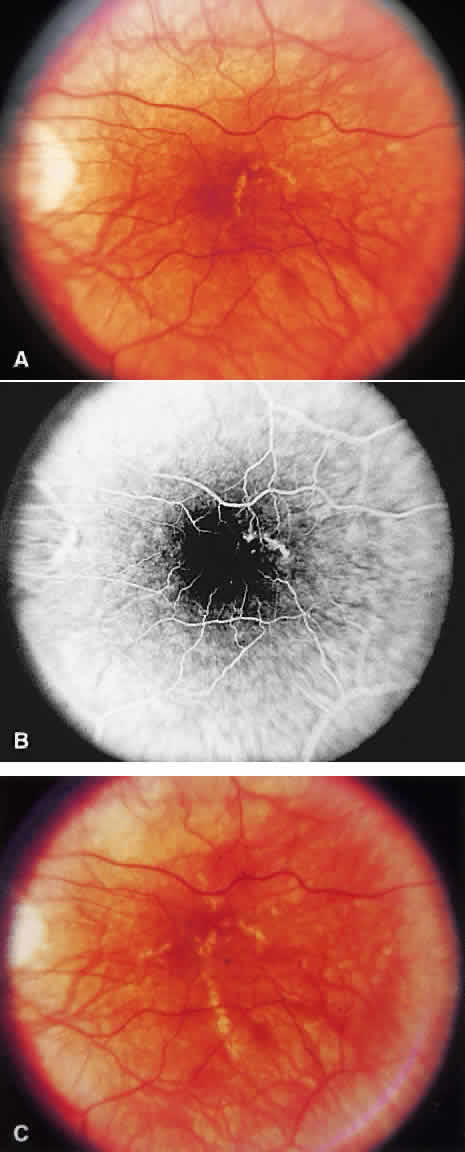

SRNV may be associated with a previous area of histoplasmosis scarring (Fig. 15). The visual prognosis is poorer for eyes with SRNV and a perifoveal choroidal scar in the fellow eye. If such a scar exists, there is a 20% to 25% chance of the development of a neovascular membrane in 5 years; without such scars, there is only about a 4% chance of SRNV developing from the scarring around the disc.102,103 A follow-up evaluation of patients in the MPS showed that choroidal neovascularization is often preceded by an atypical histo spot.104 Macular SRNV, however, has been described in the absence of preceding atrophic scars.105 Prognosis for vision remains good: 81% can be expected to have 20/20 or better acuity after 5 years when the fellow eye has had CNV.104

Fig. 15. A. Histo spots are noted in association with choroidal neovascularization (CNV) membrane (dirty green) and subretinal hemorrhage. B. Corresponding angiogram shows transmitted fluorescence from histo spots, mild peripapillary atrophy, blocked fluorescence from subretinal hemorrhage, and CNV in association with a histo spot. C. After laser treatment to the CNV complex, hemorrhage has resolved and there is early scarring of the CNV membrane. D. Corresponding angiogram shows staining of the scar.

Laser treatment has been shown to be an effective treatment of SRNV associated with presumed ocular histoplasmosis syndrome and located 200 μm or more from the center of the foveal avascular zone.106 In the ocular histoplasmosis section of the MPS, 34% of untreated eyes versus 9% of treated eyes suffered severe visual loss of six or more lines after 18 months of follow-up. Corticosteroids are not believed to be of benefit for the associated SRNV.